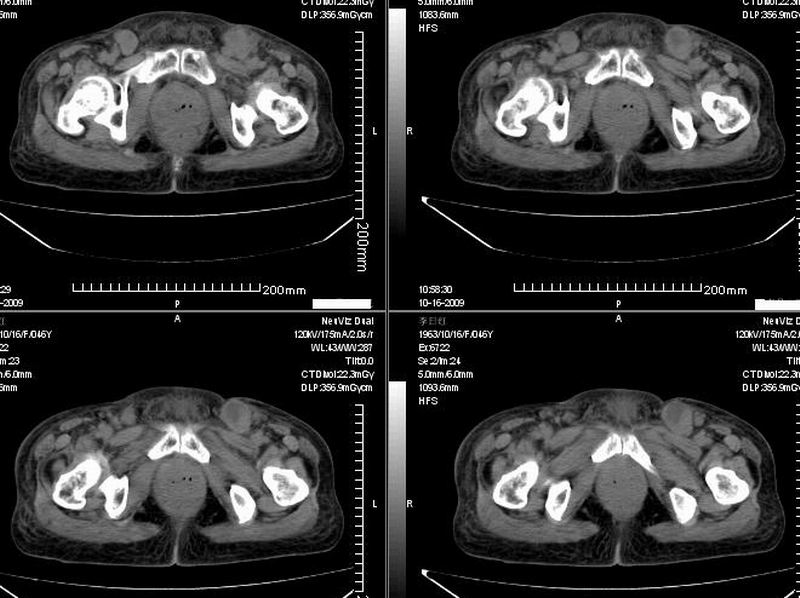

女:46y:一年前宫颈癌术后,现右下腹抚及肿块。

考虑宫颈癌术后复发周边侵犯/右中下腹及双侧腹股沟淋巴结转移。

考虑宫颈癌术后复发周边侵犯并右中下腹转移灶及双侧腹股沟淋巴结转移。